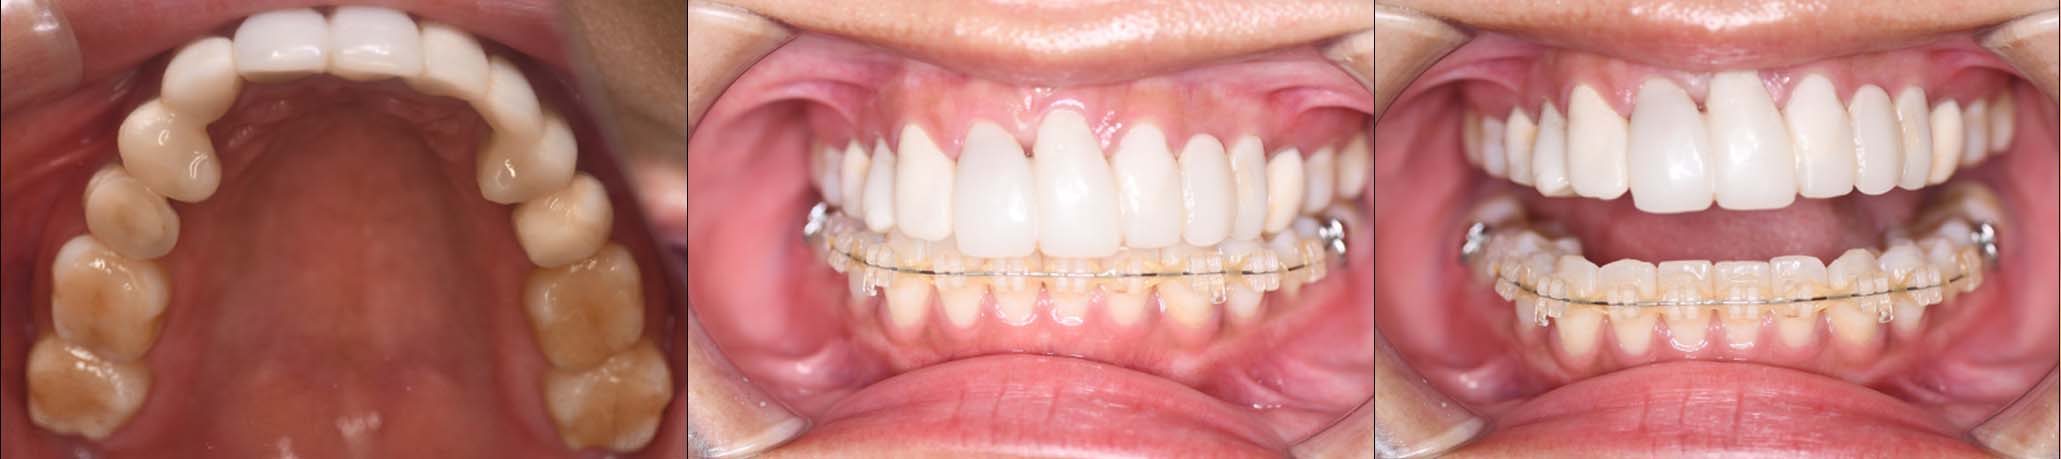

スプリント使用後、

補綴治療をした症例

治療内容 ①スプリントを装着

②副子を装着

③2024年4月 口腔内反映開始

④副子を入れた状態の所まで咬合を挙上

(バイトアップ)

⑤2024年5月 上顎前歯部8本へ仮歯(TEK)

を装着